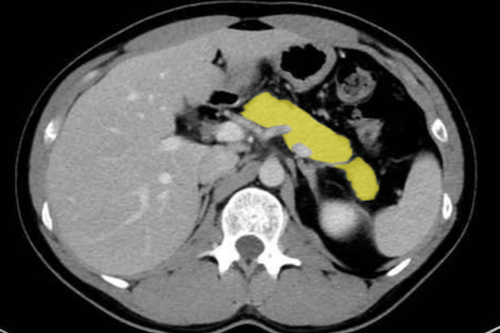

췌장 / 비장 / 비장 주변 질환

- 급성 또는 만성 췌장염

췌장의 비후, 주변 지방 음영 변화, 액체 고임(농양 또는 낭종) 등을 관찰할 수 있습니다 . - 췌장암 / 낭종성 병변

종괴 형태, 조영 증강 양상, 국소 침윤, 주변 조직 침범 여부 등을 확인할 수 있습니다 . - 비장 질환